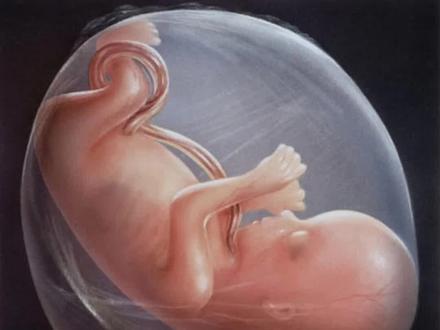

你有没有想过这样一个问题,孕妇怀孕破水为啥叫羊水?破了为啥不叫人水或者其他水?羊水为什么叫羊水?羊水是宝宝的生命之水,之所以被称为羊水,有这么几种说法,第一,羊水这个词是一个古名词,在古字中,羊和羊是相通的, 羊代表太阳,也就是代表人类的生命。开始最开始称羊水,后来经转化演变,慢慢变成了羊水。第二,传说羊水起源于羌族, 以前的人们对羊特别喜爱,因此将羊水比喻成婴儿水。第三,根据西医的说法,是羊膜内的液体。古希腊人认为宝宝出生时包裹在身上的膜和羊肠相似度很高,因此把羊膜里面的液体称为羊水。不管是哪种说法,如今我们都习以为 长的称之为羊水了。羊水是供养宝宝生命不可或缺的重要部分,其中主要成分是水,水含量达到百分之九十八, 同时也存在有少量的无菌眼泪、有积物荷尔蒙以及脱落的胎儿的细胞。羊水到底有什么作用?首先,孕妇的身体在活动时难免大幅度摇晃,肚子里的羊水就能对胎儿起到缓冲和保护作用,减少外部给宝宝带来的伤害。 第二,羊水能起到一个润滑剂的作用,防止宝宝在子宫内发生肢体粘连,促进健康发育。第三, 宝宝通过吞咽羊水,排出羊水来锻炼自己的呼吸和消化能力,从而促进肺部和消化功能的发育,并且实现羊水的循环。羊水是恒温的,可以稳定子宫内的温度,让宝宝处在一个相对适宜的温度里面,避免 受到外界温度的影响。第五,羊水能缓解胎儿在子宫内的活动给妈妈带来的不适感。第六,妈妈生产时,羊水能起到一定的润滑的作用,也减轻了新生胎儿与皮肤的摩擦。 第七,羊水形成的水能还能缓和子宫颈的扩张。第八,羊水中的抑菌物质能降低生产时妈妈和宝宝感染的几率。现在还有一些临床开始研究从羊水中提取干细胞治疗疾病。 羊水中的细胞含量本身不多,更多更丰富的钙细胞都在胎盘和脐带中,生命起源之处都是珍贵的宝贝。

你有没有想过这样一个问题,孕育着胎儿的水为什么要叫羊水,而不是其他的水?其实羊水是宝宝的生命之水。 之所以被称为羊水,有这么几种说法,第一是谐音,说,谐音又分为两种,一种是羊水,意思非常直白,取滋养、 养育婴儿的意思。另外一种是羊水,这个词是一个古名词,在古字中,羊和羊是相通的,羊代表太阳, 也就是代表人类的生命,起初称之为羊水,后来经转化演变,慢慢变成了羊水。第二,传说羊水起源于羌族,以前的人们对羊特别喜爱,因此将羊水比喻成婴儿水。第三,根据西医 的说法,是羊魔内的液体。古希腊人认为宝宝出生是包裹在身上的魔,和羊肠相似度很高,因此把羊魔里面的液体称为羊水。不管是哪种说法, 如今我们都习以为常地称之为羊水了。羊水是供养宝宝生命不可或缺的重要部分,其中主要成分是水,水含量达到百分之九十八, 同时也存在着少量的无机盐类有机物、荷尔蒙以及脱落的胎儿细胞。那么你知道羊水到底有什么作用吗?咱们下期再聊这个话题,老铁们可以在评论区留言。

充满在羊魔腔内的液体称为羊水。之所以叫羊水,是因为其在羊魔腔内。此外,在古代,羊和羊是相通的。羊代表着生命的开始,羊水代表着宝宝的生命水,这也代表着对宝宝的祝愿和期盼。